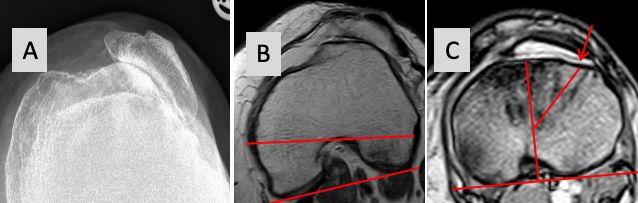

8.2 Functional derotation inside the joint

By using the TTA of Insall and minimum PS constraint, the tibia will make an internal rotation with the trial components inside (Fig 25 A and B). This brings the TT under the trochlea and reduce the pathological TT-TG to less than 5 mm [34]. Sometimes the insertion of the PE insert is difficult and can be performed only by forced internal rotation of the lower leg. CR and mobile bearing inserts do not work with this technique. Maximum 30° of functional derotation is possible, otherwise the forefoot progression angle gets negative with internal rotation of the forefoot and the collateral ligaments tension is changed.